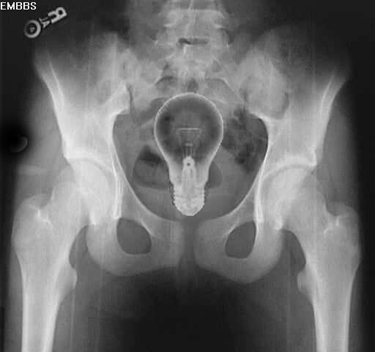

“Well, either this kid has a lightbulb up his butt, or his colon has a great idea!”–Dr. Cox (Scrubs)

“They can have my 100 watt incandescent when they pry it from my cold dead arse!!”

Fake. The bulb is perfectly oriented and centered.